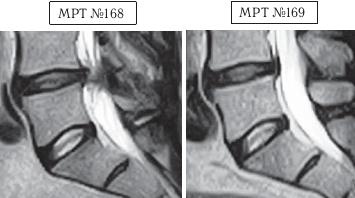

На МРТ № 168 наблюдается состояние поясничного отдела позвоночника: секвестрированная грыжа межпозвонкового диска в сегменте LIV-LV с разрывом задней продольной связки, отрывом фрагмента секвестра с его дорсальной миграцией, абсолютный стеноз спинномозгового канала. Такое состояние — последствия лечения протрузии межпозвонкового диска с применением хиропрактической техники манипуляций на позвоночнике (мануальная терапия). На МРТ № 169 — состояние поясничного отдела позвоночника после лечения методом вертеброревитологии: отсутствие грыжи межпозвонкового диска в сегменте LIV-LV, отсутствие стеноза спинномозгового канала. Разные люди, разные случаи. В следующем примере столь значительное ухудшение состояния здоровья пациента было спровоцировано его индивидуальными занятиями на приспособлении для вытяжения позвоночника. А всё началось с банального желания избавиться от «стартовых» болей в пояснице. ![]() На МРТ № 170 наблюдается состояние поясничного отдела позвоночника: ретроспондилолистез LV (соскальзывание позвонка относительно другого позвонка), протрузии межпозвонковых дисков в сегментах LII—LIV и LIV-LV На МРТ № 171 наблюдается состояние поясничного отдела позвоночника: ретроспондилолистез LV увеличение протрузии межпозвонкового диска в сегменте LIII-LIV, образование секвестрированной грыжи межпозвонкового диска в сегменте LIV-LV с разрывом задней продольной связки, абсолютный стеноз на этом уровне. На МРТ № 172 — состояние поясничного отдела позвоночника в середине первого курса лечения методом вертеброревитологии (после двух недель от начала лечения): наблюдается положительная динамика, выраженная ретрузия секвестра грыжи межпозвонкового диска в сегменте LIV-LV, визуально прослеживается увеличение высоты межпозвонкового диска в том же сегменте, что свидетельствует о начавшемся активном процессе его восстановления, значительное уменьшение стеноза спинномозгового канала на данном уровне. «Стартовые» боли в пояснице в основном проявлялись, когда данный человек выходил из автомобиля. В течение нескольких минут они ему «мешали распрямить спину». Потом, правда, исчезали и могли вновь напомнить о себе после длительного сидения в кресле или в автомобиле. Но так как пациент в силу своих служебных обязанностей вынужден много сидеть (проводить многочасовые совещания, работать с бумагами и так далее), то, естественно, эти боли его раздражали. Как говорится, чрезмерная бюрократия вредна не только для здоровой экономики страны, но и для здоровья самого бюрократа. После того как ему сделали снимок (МРТ № 170) и выяснили, что данные боли возникают вследствие развития спондилолистеза, то, естественно, пациенту предложили операцию с целью стабилизации поражённого сегмента. Не поверив нашим эскулапам (нет пророка в своём Отечестве), пациент отправился в знаменитую клинику за границу, где «светилы» зарубежной медицины (в основном наши бывшие соотечественники) также подтвердили необходимость в оперативном разрешении данной ситуации. Однако пациент, хотя досконально и не разбирался в вопросах заболеваний позвоночника, но зато умел делать выводы из чужих ошибок. Менее двух лет назад его коллега после операции на позвоночнике (кстати, в той же зарубежной клинике) променял солидную должность и кресло «большого начальника» на инвалидность, поэтому этот человек оперироваться не стал и решил пойти другим путём. Приехав домой, он начитался различной рекламы по лечению остеохондроза и его осложнений и выбрал для себя наиболее удобный способ лечения, который вполне устраивал его в режиме служебной деятельности. Обратившись в специализированный медицинский центр по лечению остеохондроза, он приобрёл там специальное приспособление для вытяжения позвоночника и получил от специалистов данного центра комплекс упражнений на нём. Месяц добросовестных тренировок, совмещённых с вытяжением позвоночника (согласно рекомендациям специалистов!) дал свои закономерные результаты. «Стартовые» боли в пояснице при подъёме, из-за которых и началась вся эта история, пациента уже не волновали, поскольку он вообще перестал не только сидеть, но даже ходить. Естественно, начались и другие проблемы в позвоночнике. Следующий месяц в стационаре неврологии (в хирургию упорно не хотел) дали положительные результаты: острые боли постепенно утихали от воздействия сильных обезболивающих препаратов. Пациент смог вставать на ноги, с посторонней помощью проходить от пяти до десяти метров. Сделали снимок (МРТ № 171), на котором выявили секвестрированную грыжу межпозвонкового диска в сегменте LIV—LV с разрывом задней продольной связки. До этого времени ему не могли провести обследования из-за некупируемых болей, а от наркоза он отказывался. Врачи диагностического центра, проводившие МРТ-обследование, посоветовали ему обратиться ко мне. В этот же день, когда больного привезли ко мне на приём, я взялся за эту работу. Через две недели лечения методом вертеброревитологии данный пациент смог самостоятельно приезжать на автомобиле (за рулём). По своей инициативе он сразу сделал ещё одно МРТ (результат интересный, МРТ № 172), на котором можно наблюдать процесс обратного движения грыжи, то есть когда фрагменты выпавшего межпозвонкового диска «заходят» обратно в межпозвонковый диск. Другими словами — процесс ретрузии секвестра грыжи межпозвонкового диска в сегменте LIV-LV а также активный процесс восстановления самого диска. ![]() На МРТ № 173 (увеличенный фрагмент МРТ,№ 171) наблюдается секвестрированная грыжа межпозвонкового диска в сегменте LIV-LV с разрывом задней продольной связки, абсолютный стеноз на этом уровне. На МРТ № 174 (увеличенный фрагмент МРТ № 172) наблюдается состояние межпозвонкового диска в середине первого курса лечения методом вертеброревитологии (после двух недель от начала лечения): положительная динамика, выраженная ретрузия секвестра грыжи межпозвонкового диска в сегменте LIV-LV Вот ещё одни снимки МРТ другого пациента, которые наглядно демонстрируют процесс ретрузии грыжи диска. ![]() На МРТ № 175 наблюдается состояние поясничного отдела позвоночника: компенсированная протрузия, грыжа Шморля в сегменте LIV-LV, спондилёз, гипертрофия задней и передней продольных связок, грыжа межпозвонкового диска сегменте LV—SI, стеноз спинномозгового канала. |